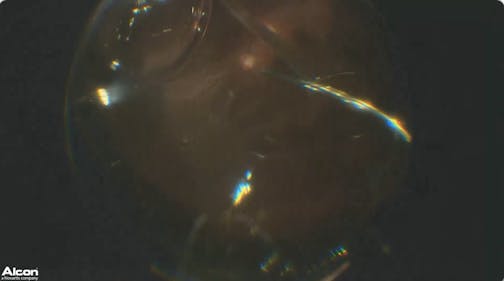

Dense Cataract

Anat Loewenstein, MD